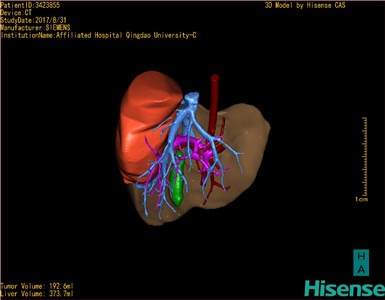

将0.625mm双源薄层CT资料的静脉期和动脉期Dicom格式文件导入海信CAS系统。

通过调节窗宽窗位调整CT序号,对肝实质,胆囊,下腔静脉,肿瘤,肝动脉、门静脉及肝静脉等进行三维重建;系统自动计算肝脏体积。

模拟手术操作,自动计算切除肿瘤体积。肝脏体积为373.7ml,肿瘤体积是192.6ml,是肝脏体积的0.5倍,通过比对2-3岁正常肝脏体积为475.97±99.7ml,通过术前模拟手术,精准判断切除后剩余肝脏体积能耐受,避免肝衰竭发生。

术前三维重建:

重建图片